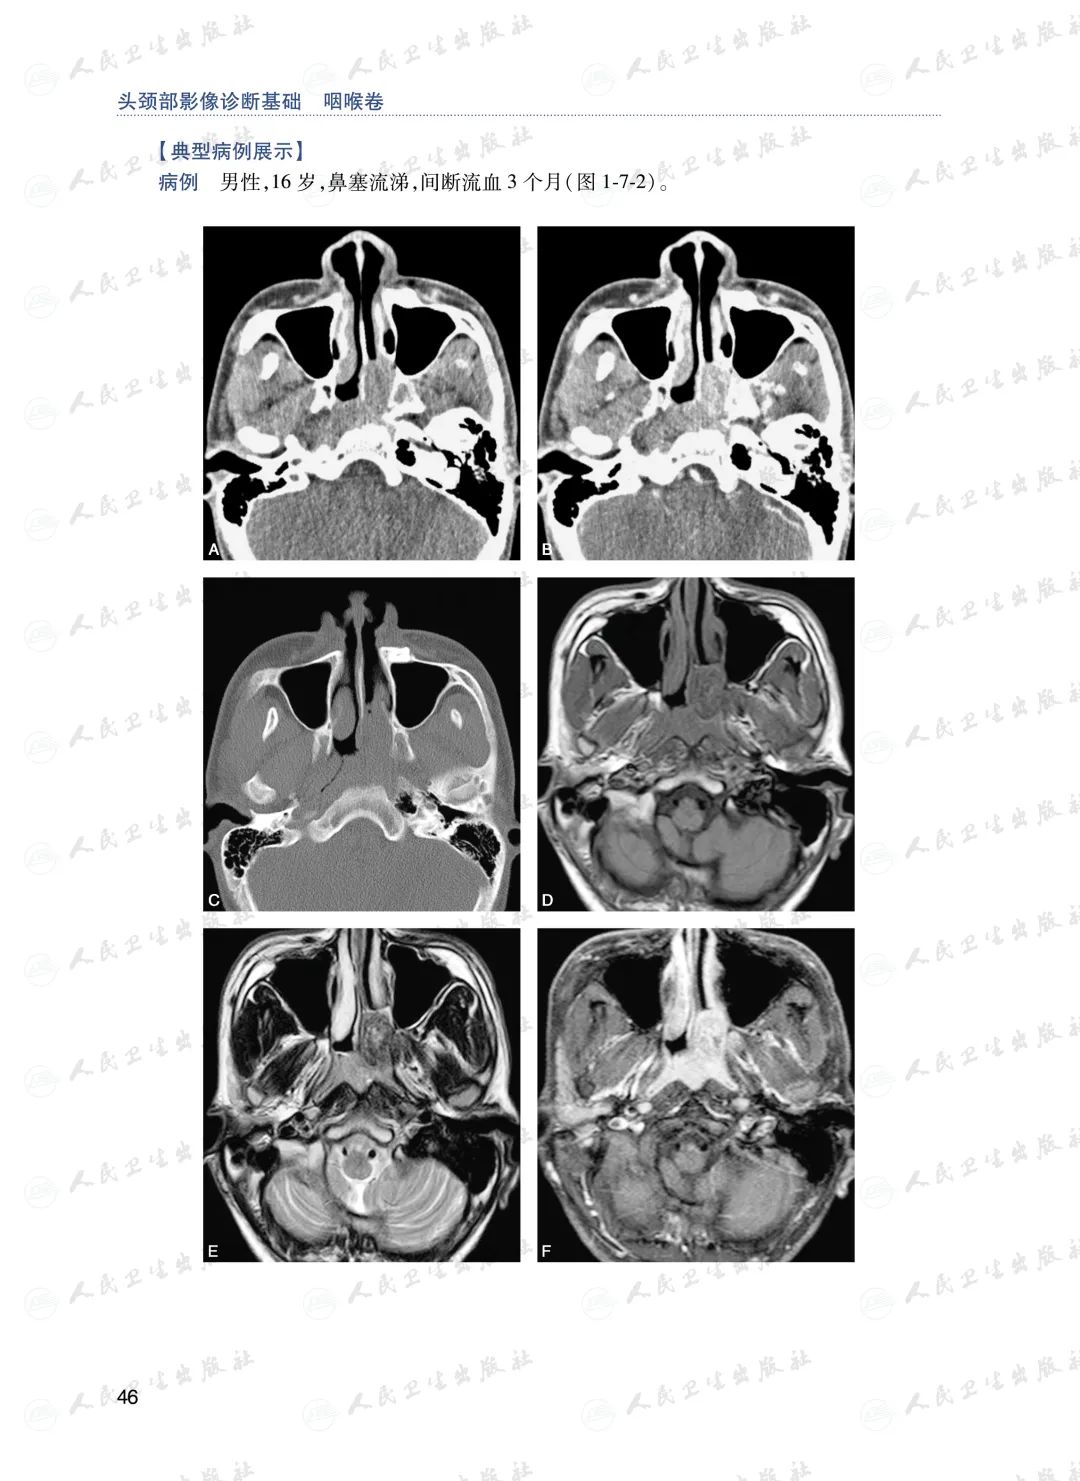

◆样章试读◆